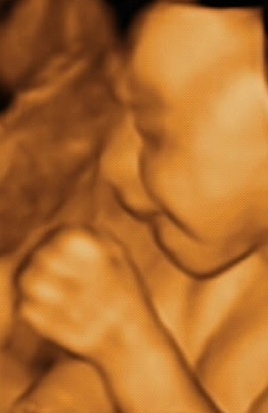

Ecografie

Ecografie (2D, 3D e

4D

) effettuate durante la gravidanza di Alice